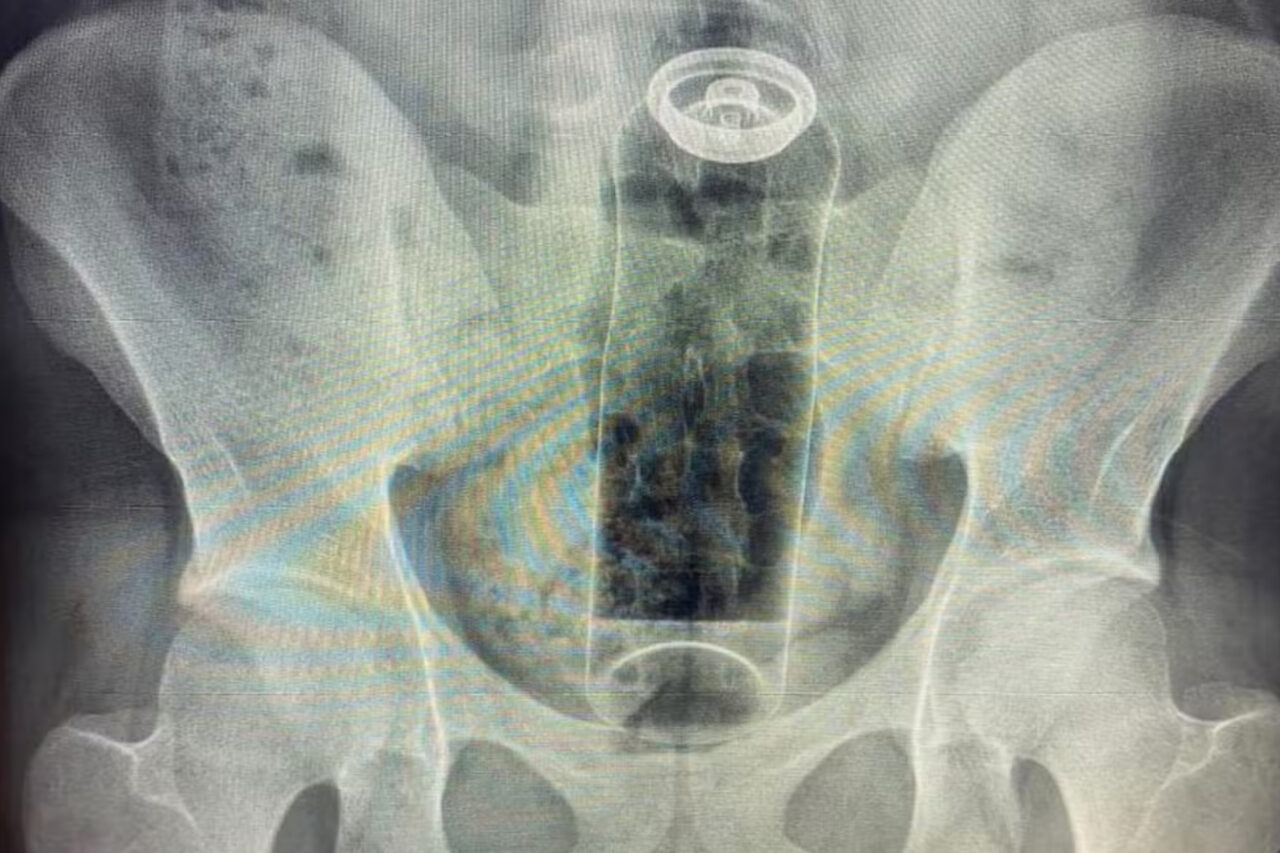

De acordo com o médico Daniel Brosco, cirurgião coloproctologista, o paciente tinha 19 anos e contou que colocou o desodorante no ânus durante uma “brincadeira” sexual. A embalagem, porém, acabou subindo para o reto e não conseguiu ser retirada em casa.

A fantasia não é um problema. O problema é não usar objetos específicos para isso. Imagina se o conteúdo da embalagem vaza ou se o objeto sobe de uma forma que exige cirurgia para retirar? Já tive pacientes que acabaram com infecções graves e morreram — Daniel Brosco, cirurgião coloproctologista.

O médico conta que os casos têm sido cada vez mais comuns e que, nos últimos meses, já atendeu pacientes em que precisou retirar objetos como batata, partes de uma cadeira, garrafa de vidro e plug anal.

Como isso acontece? O intestino pode “sugar” esses objetos por causa dos movimentos peristálticos — contrações involuntárias responsáveis pelo funcionamento do órgão — ou pelo vácuo criado em áreas como o reto.

Com isso, o objeto pode ficar preso rapidamente. O médico alerta que é preciso buscar atendimento hospitalar o mais rápido possível e não tentar soluções caseiras, como o uso de laxantes. A contração provocada pelo medicamento pode agravar ainda mais a situação.